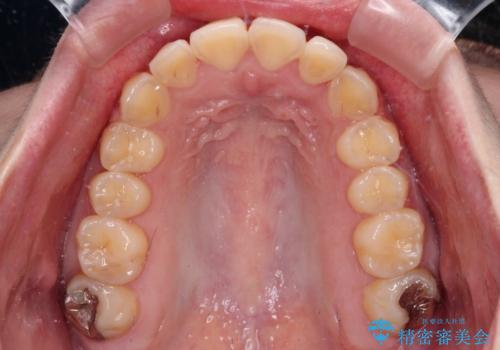

- 前歯のデコボコとクロスバイトが気になり、インビザラインによる矯正治療を希望して来院された患者様です。

上顎側切歯(上の真ん中から2番目の歯)が舌側転位している場合、無理して動かそうとすると歯髄壊死を起こすリスクが高い印象があります。

インビザライン単体でも治療は可能ですが、安全策としてインビザラインで歯列を移動する前に上顎前歯をワイヤー矯正で整え、その後上下歯列をインビザラインにて矯正治療を行うこととしました。

舌側転位している側切歯特有の、切縁の位置が不揃いであったり、根元が内側に引っ込んだ状態であったりという、インビザライン独特の仕上がりになることなく、きれいに整った歯列とすることができました。